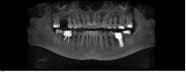

Case 1: Osteotome sinus lift with simultaneous implant placement

A 53-year-old female with a medical history of hypothyroidism, seasonal allergies, and asthma taking Synthroid and Singula presented to my office with pain in No. 3, failed root canal therapy, and a fracture. The tooth was deemed hopeless and extraction and implant placement was treatment planned. Under local anesthesia, tooth No. 3 was sectioned into three pieces and extracted. The sockets were debrided, filled with gel foam, and closed with chromic gut sutures. Healing was uneventful. The patient did not return for two years for follow-up. A CT scan was taken, which confirmed that approximately5 mm of bone remained below the floor of the sinus. After reviewing the options with the patient, a treatment plan of an internal sinus lift (osteotome), bone graft, platelet-rich fibrin (PRF) and simultaneous implant placement was agreed upon. Under local anesthesia, a full thickness flap with two vertical releasing incisions was performed at tooth No. 3 site. A trephine bur was used to a depth of 4 mm. An osteotome was then employed to infracture the bone core, which remained attached to the Schneiderman membrane. A bone graft consisting of DFDBA, anorganic bovine bone, and PRF was used in the osteotomy to increase the vertical bone height using sequential osteotomes. After sufficient elevation, a 7x9 tapered implant was placed on low speed to 50% of the implant depth. The remaining placement of implant was done with a hand torque on 50 ncm to allow for further expansion of the alveolar housing. A healing abutment was placed using the principles of platform switching. Healing was uneventful, and integration was successful.

Case 1: Implant and osteotome bone graft through the socket with Southern Implant